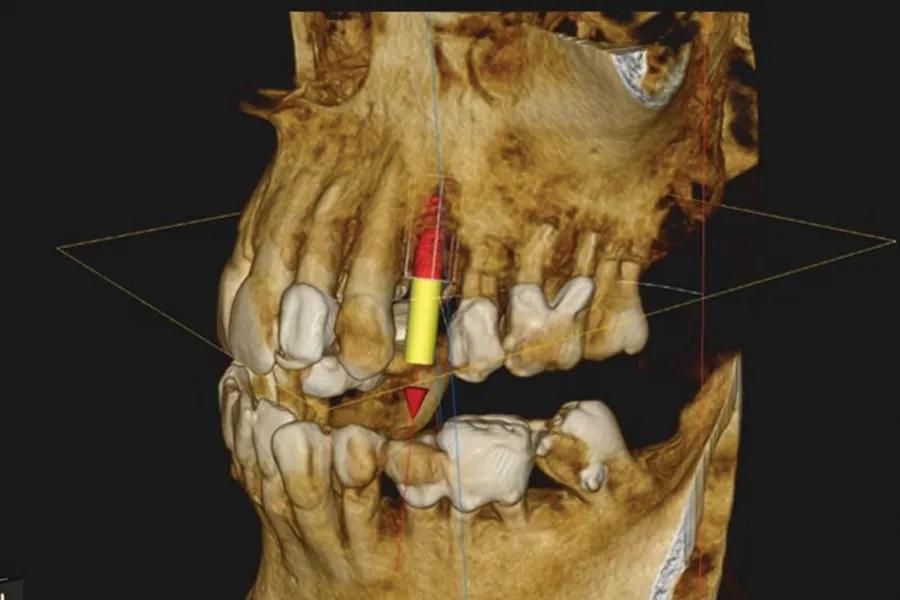

Пациент мужского пола 68 лет был направлен эндодонтистом с диагнозом симптоматический необратимый пульпит с нормальными периапикальными тканями и значительной потерей костной ткани с вовлечением фуркации у первого премоляра верхней челюсти слева (зуб № 2.4). Из-за состояния пародонта была показана реабилитация с помощью имплантационной реставрации. Конусно-лучевая компьютерная томография (КЛКТ) выявила потерю кости с дистальной стороны пораженного зуба, размером 5 мм в ширину и 9 мм в длину соответственно, с вовлечением альвеолярного костного гребня (Фото 1 – Фото 4).

Фото 4. Предоперационный сагиттальный срез КЛКТ первого премоляра верхней челюсти слева, демонстрирующий область рентгенопрозрачности, вовлекающую более двух третей корня, включая пришеечную область и альвеолярный костный гребень.

Через 5 месяцев после удаления были выполнены контрольные КЛКТ и интраоральное сканирование, а также завершено цифровое планирование имплантации (Фото 11).

Фото 11. 3D-позиционирование имплантата при цифровом планировании.